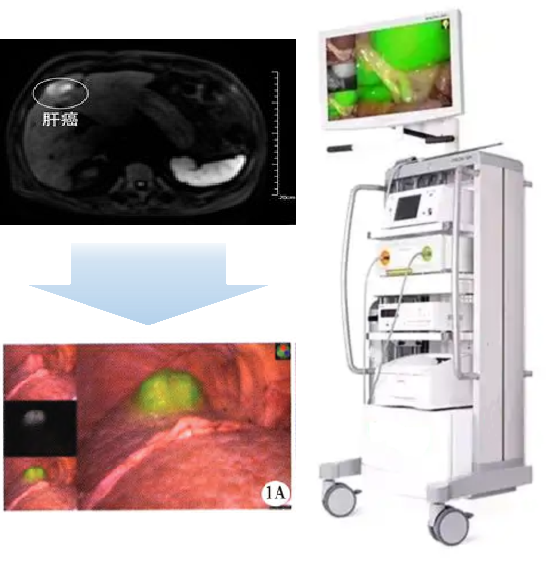

(二)适应症:本品拟用于原发性肝癌患者的术前诊断及术中导航。

PL002是浙江普利药业有限公司研发的荧光/磁共振双模态造影剂,开发荧光/磁共振双模态造影剂成为提高原发性肝癌手术效率的有效方案。双模态造影剂的荧光成像能力可用于肝癌术中荧光导航,而磁共振增强能力可用于在术前判断肝脏代谢能力,推测肿瘤及肝脏对造影剂的摄取情况,提高肿瘤诊断精度,降低术前规划难度。

PL002相较于吲哚菁绿具有明显优势。目前吲哚菁绿在临床使用中存在给药到手术时间不确定的问题,可能造成病灶与正常组织对比度不足,影响术中的病灶的判断,PL002采用独特的钆络合物与荧光分子共价键结合的分子结构设计,这种设计能够让医生在术前通过磁共振成像确定造影剂在病灶中的聚集情况,进而针对患者个体情况来对手术时间进行规划。同时,由于PL002体内更为稳定,在荷瘤小鼠模型中同等条件下荧光成像效果维持时间长于现有荧光造影剂,也保证了其在临床应用中具有更宽的手术窗口。